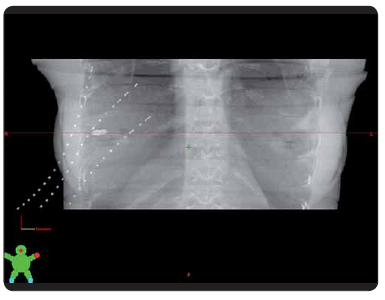

Po lokalizaci cílového objemu se na BRT sále zavádí do prsu ozařovací katetry pomocí dutých jehel. Těmito jehlami jsou protaženy ozařovací katetry, které slouží k zavedení Ir (iridiového) zdroje pro ozáření. U pacientky je provedeno plánovací CT vyšetření se zavedenými katetry. Pro správnou lokalizaci těchto katetrů je nutné je při CT vyšetření zviditelnit. K tomu slouží rentgenkontrastní markery, které se před CT vyšetřením vloží do katetrů, a umožňují tak správně zakreslit průběh katetrů pro potřeby plánování. Po změně výrobního programu bylo možné u dodavatelské firmy zakoupit pouze nové markery, které však již neodpovídaly původně používaným markerům. Nové markery mají speciální provedení, bohužel však nemají stejnou tloušťku v celé délce průběhu, proto nejsou v některých CT řezech vidět, a marker tak v nich nemůže být zcela jednoznačně identifikován.

Provedli jsme několik zkušebních CT vyšetření s různými tloušťkami řezu s pomocí speciálního antropomorfního fantomu, do kterého jsme umístili zkušební katetry i s novými markery. Z každého takového souboru CT řezů byla v plánovacím systému vytvořena 3D rekonstrukce a následně jsme se pokoušeli správně identifikovat jednotlivé katetry. Nejpřesnější zobrazení průběhu katetrů ve fantomu je možné při tloušťce řezu 1 mm v sekvenčním režimu. Řezy tloušťky 3 mm se jeví jako nedostačující. Pro CT vyšetření u pacientky jsme zvolili tloušťku řezů 2 mm.